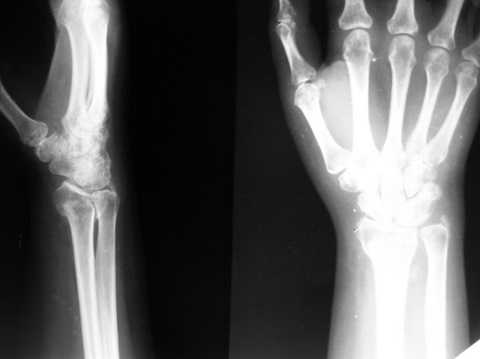

Уважаемые коллеги, обращаюсь к вашему опыту. Обратилась женщина 45лет, профессия - швея, травма 24.02.07 вколоченный перелом правого луча (см Ргр )

на Ргр нарастают явления остеопороза, не смотря на прием препаратов кальция.

AL> на Ргр нарастают явления остеопороза, не смотря на прием

AL> препаратов кальция(рис.

Видимо там был оскольчатый перелом луча и шиловидного отростка

локтевой кости.

В гипсовом повязке наблюдалось вторичное смещение костных отломков по длине (при передне-заднем рентгенограмме), и при боковй проекции видно смещение отломка в дорсальном направлении и таким

образом последный дает компрессию нервов в лучезапястном канале (типа синд. Зудека)